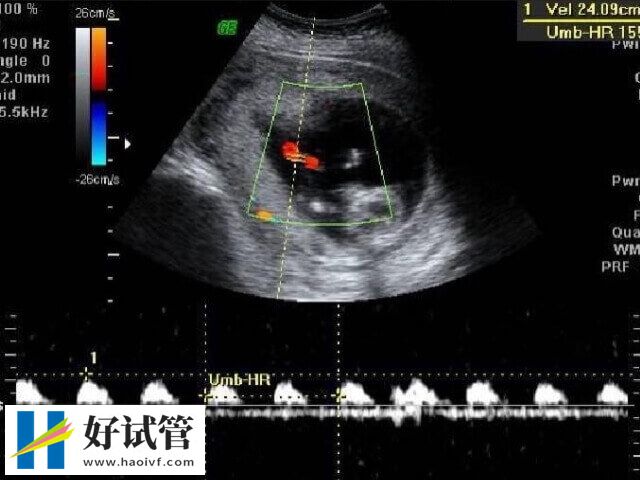

5、超声检测法:这种测量是最精确的,但缺点是太昂贵和耗时。最准确的b超检测排卵是目前发展比较简单直观的方法,尤其是月经不规律或者是需要靠促排卵的女性社会来说,可以通过准确的测量卵泡的发育研究情况,而且我们还能充分了解卵巢功能分析以及子宫内膜等。但 b 型超声波检测法需要连续一周到医院进行检测,耗时较多,成本不低。